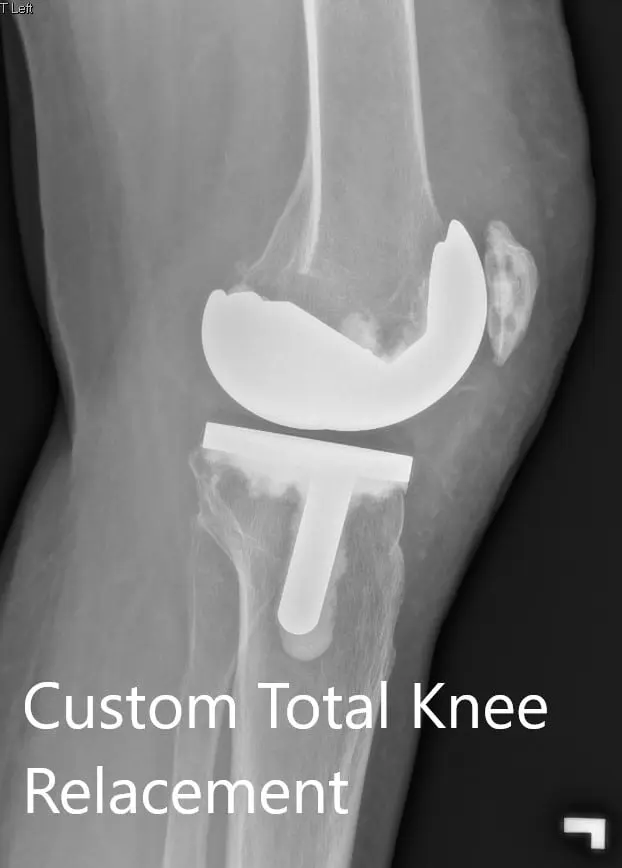

Postoperative X-ray showing the lateral view of the right and the left knee respectively

Postoperative X-ray showing the lateral view of the right and the left knee respectively - img 2